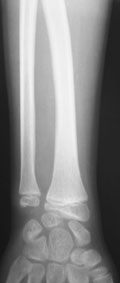

11-летний любитель лазить по деревьям 7 месяцев назад получил открытый дистальный остеоэпифизеолиз левого луча. ПХО была сделана с трудом; о репозиции, со слов, и не помышляли. Неделю назад удалось открыто адаптировать костные фрагменты, фиксировать аппаратом. Сразу сделали кортикотомию в/3 луча. Начали его удлинение. Вопрос: учитывая отсутствие дистальной зоны роста стоит ли "переудлинить" луч? Если да, то на какую величину?

как видно из Р снимков, дистальная ростковая зона повреждена. делать эпифизеодез думаю что не целесообразно. лучелоктевая косорукость преопределена, поэтому востановление придеться делать в несколько этапов. величину гиперкоррекции предусмотреть трудно не зная темпов роста, думаю что впределах 5-10мм. С уважекнием Владимир Старостенко. купянск .Харьковской. Украина

Глядя на предложенные снимки, сразу же возникает вопрос о необходимости открытого сопоставления отломков лучевой кости. Мне кажется, репозицию возможно было бы сделать и ваппарате Илизарова с использованием смещенных шарниров и этапной дистракции без выполнения разреза. Росковый хрящ, скорее всего, большей частью погиб. Но в аппарате Вы могли срепонировать и стабилизировать отломки, восстановить на время соотношение лучевой и локтевой костей в лучезапястном суставе, пусть даже дозированной осевой дистракцией.